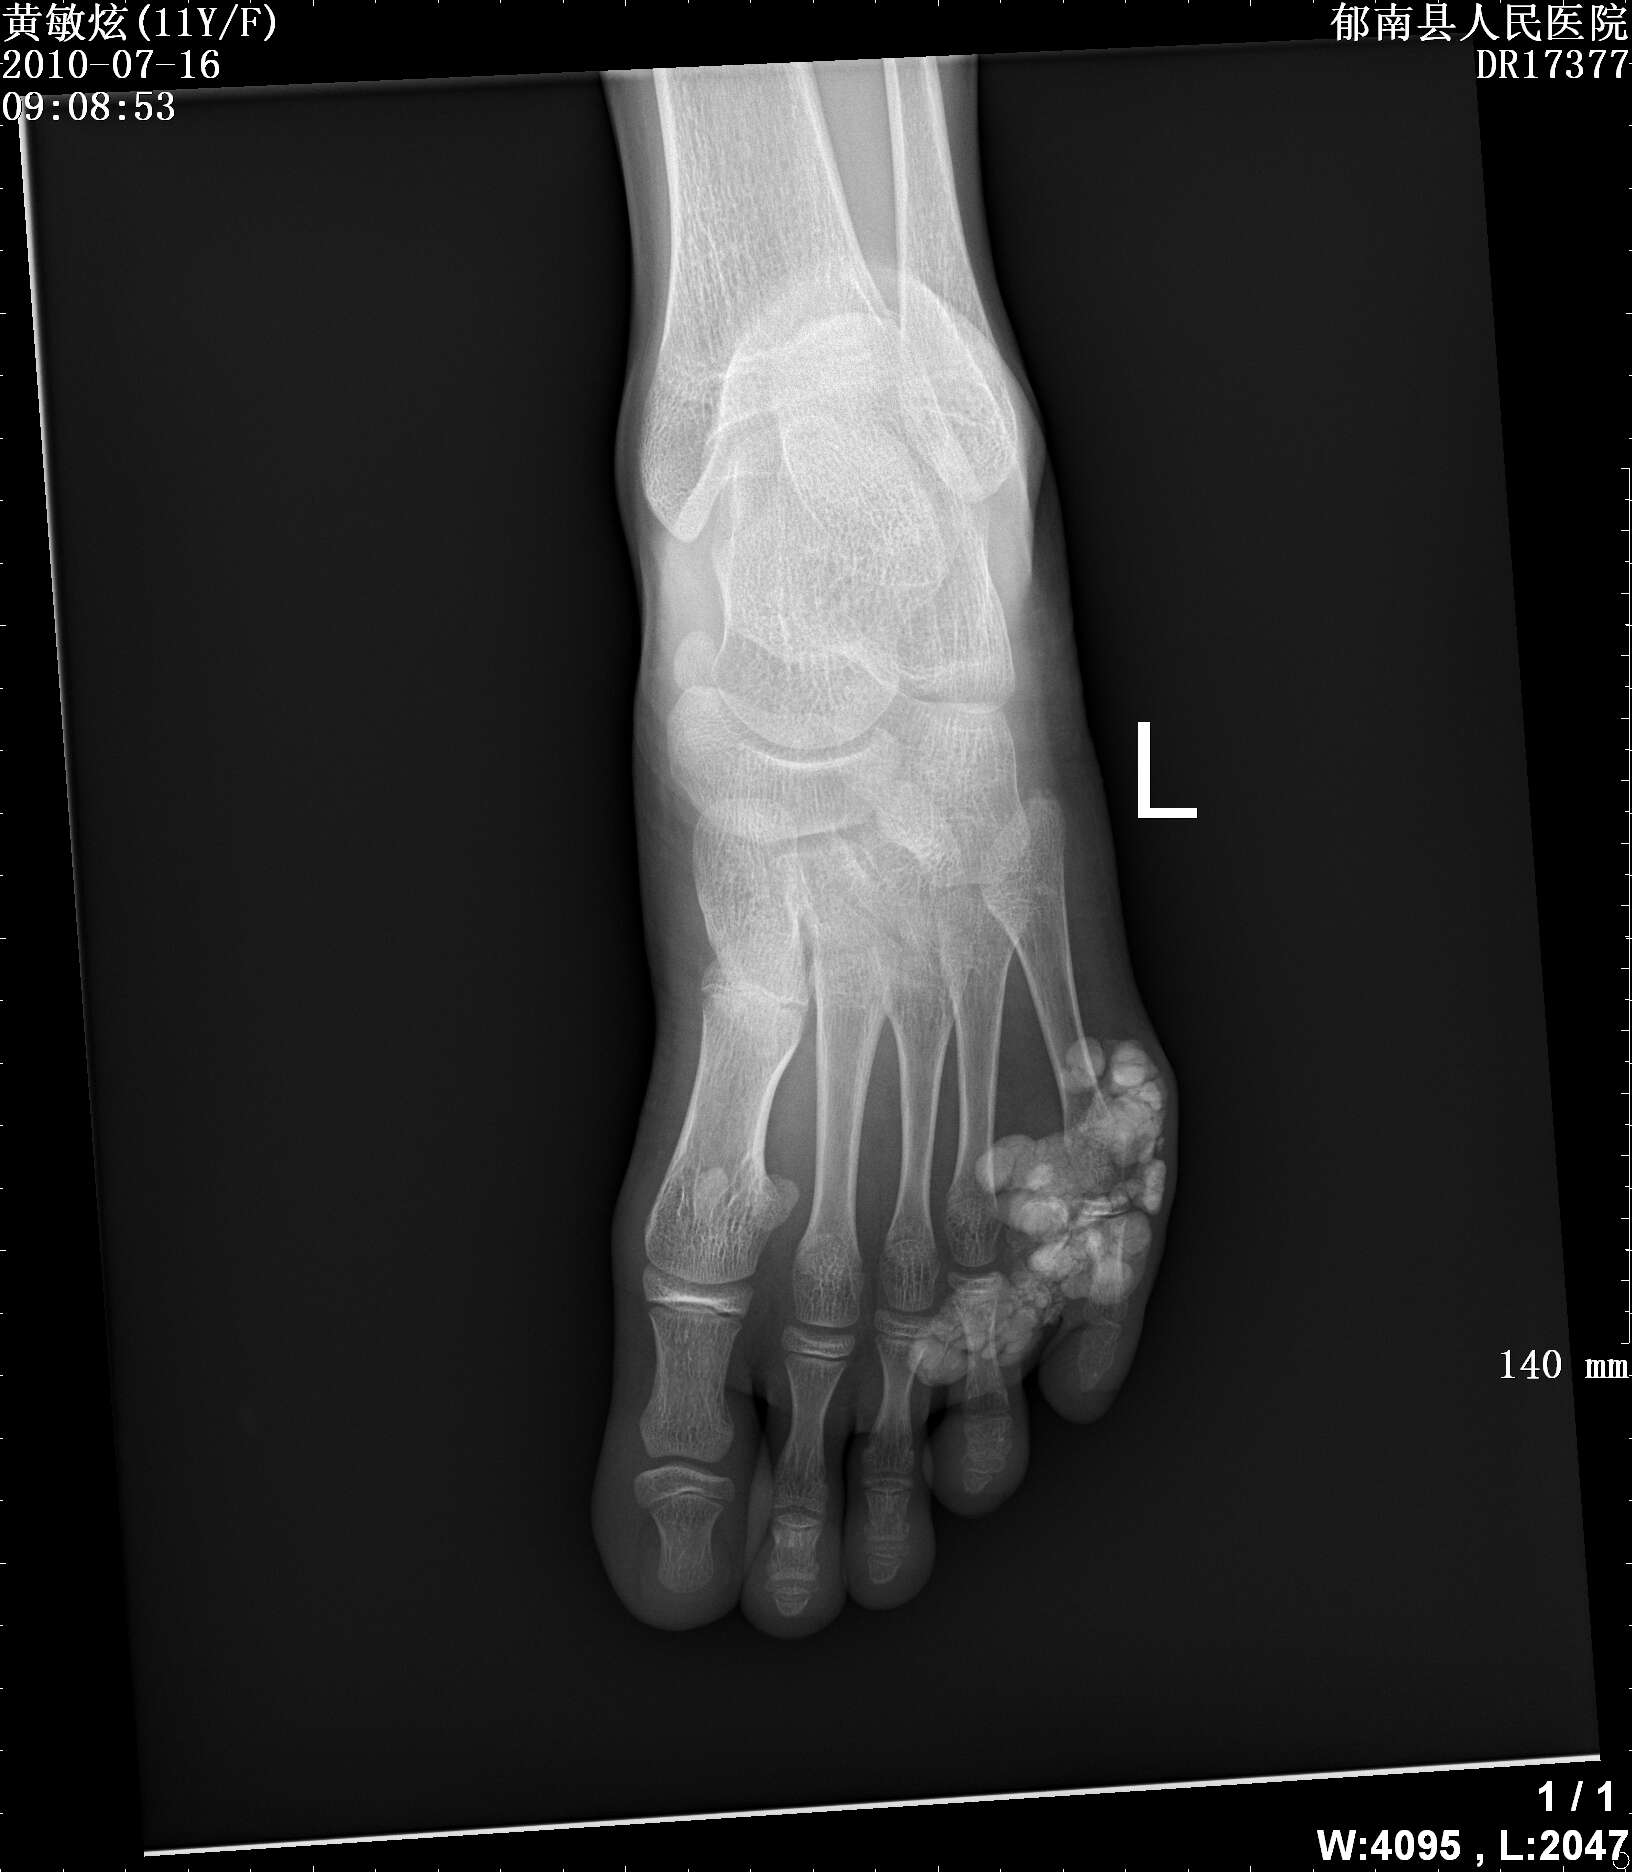

标题: PED3366:女性,11岁,发现左足第五趾肿物2年 [打印本页]

标题: PED3366:女性,11岁,发现左足第五趾肿物2年

女性,11岁,发现左足第五趾肿物2年,压之不痛,质软,无红肿,无外伤史,请各位老师指点下

病理结果是钙化性腱膜纤维瘤,请问各位老师这个病与肿瘤样钙质沉着症怎么区别呢?